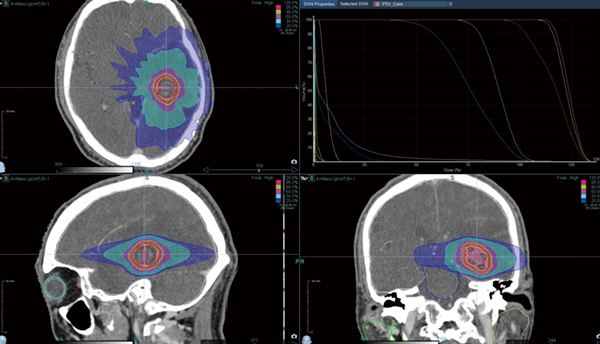

少数個脳転移に対するSRTは,前年までは全例他院に紹介していたが,Radixact導入後は当院で治療可能となり,数例問題なく施行した(図1)。

図1 原発性肺がん脳転移

SRT 28.8Gy/4fr PTV D95処方